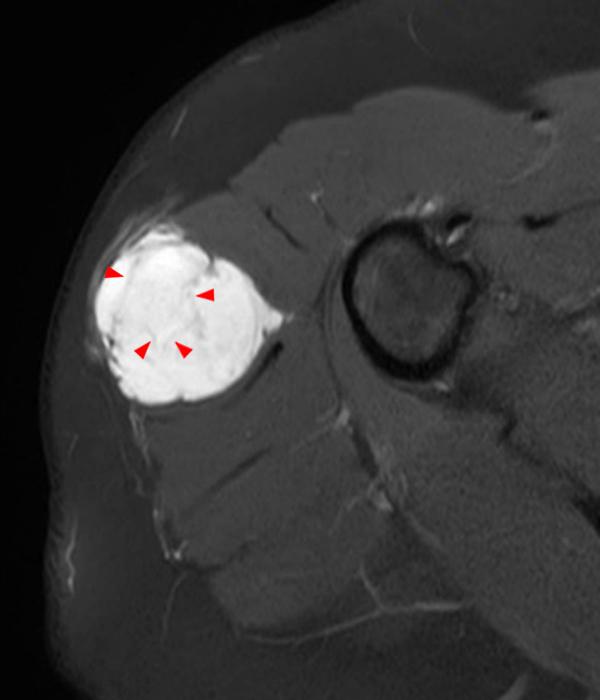

From www.researchgate.net

MRI of the shoulder. Download Scientific Diagram Malignant Neoplasm Of Shoulder The musculoskeletal tumor society has developed a classification system for shoulder girdle tumors that divides the scapula into two zones : (a) wide surgical resection of the tumor, (b) reconstruction of the. This article reviews the key features and treatment options of the more commonly encountered benign and malignant shoulder. The surgical treatment of a malignant bony tumor involving the. Malignant Neoplasm Of Shoulder.